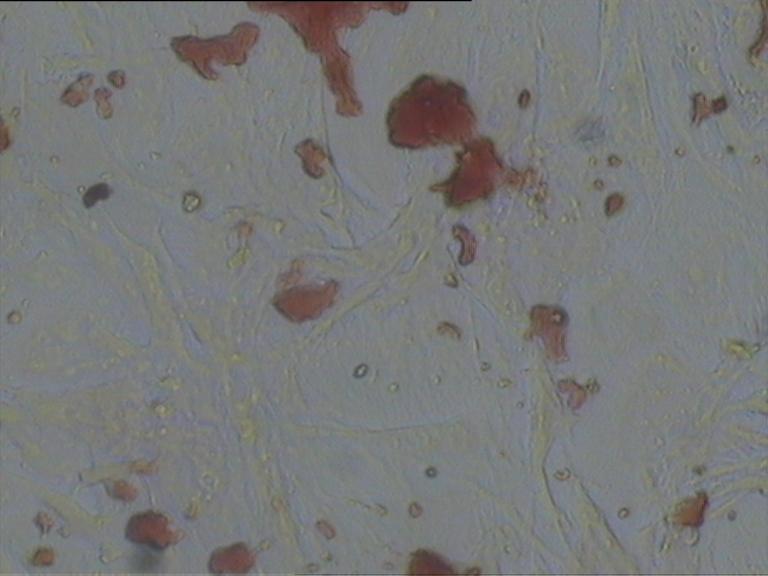

對照組

給藥組

模型組